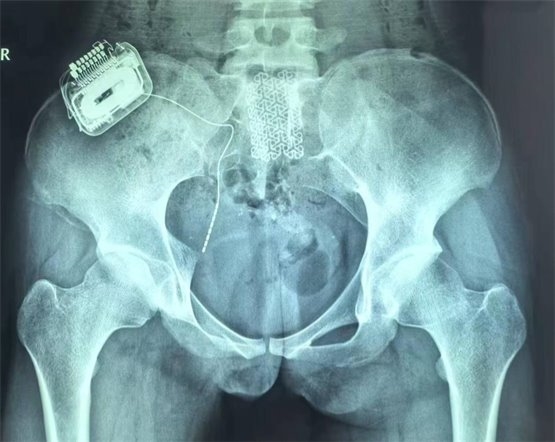

鑒于一期手術(shù)的良好療效,患者家屬?zèng)Q定進(jìn)行二期永久植入,將骶神經(jīng)電極及脈沖發(fā)生器永久性植入患者體內(nèi)。二期手術(shù)后,患者白天已經(jīng)無(wú)漏尿,夜間偶有遺尿(目前仍在調(diào)整過(guò)程中,希望通過(guò)調(diào)整合適的刺激參數(shù),后續(xù)能夠得到更好的改善);排尿費(fèi)力感減輕(術(shù)前為點(diǎn)滴狀,現(xiàn)尿線變粗,最大排尿量達(dá)220ml);肛門(mén)周?chē)鸦謴?fù)部分感覺(jué),整體改善非常顯著。

圖4為骶神經(jīng)調(diào)控術(shù)后骨盆正位片